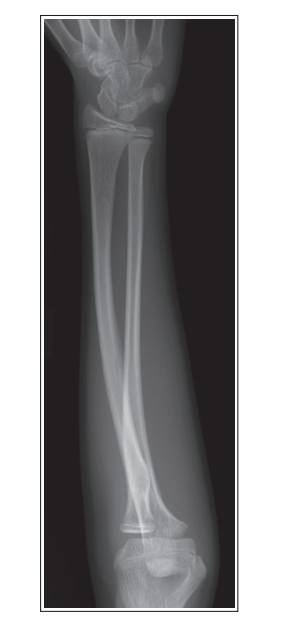

More than 1/8 of the radial head is superimposing with the ulna

Internal rotation

Less than 1/8 of the radial head is superimposing with the ulna

External rotation